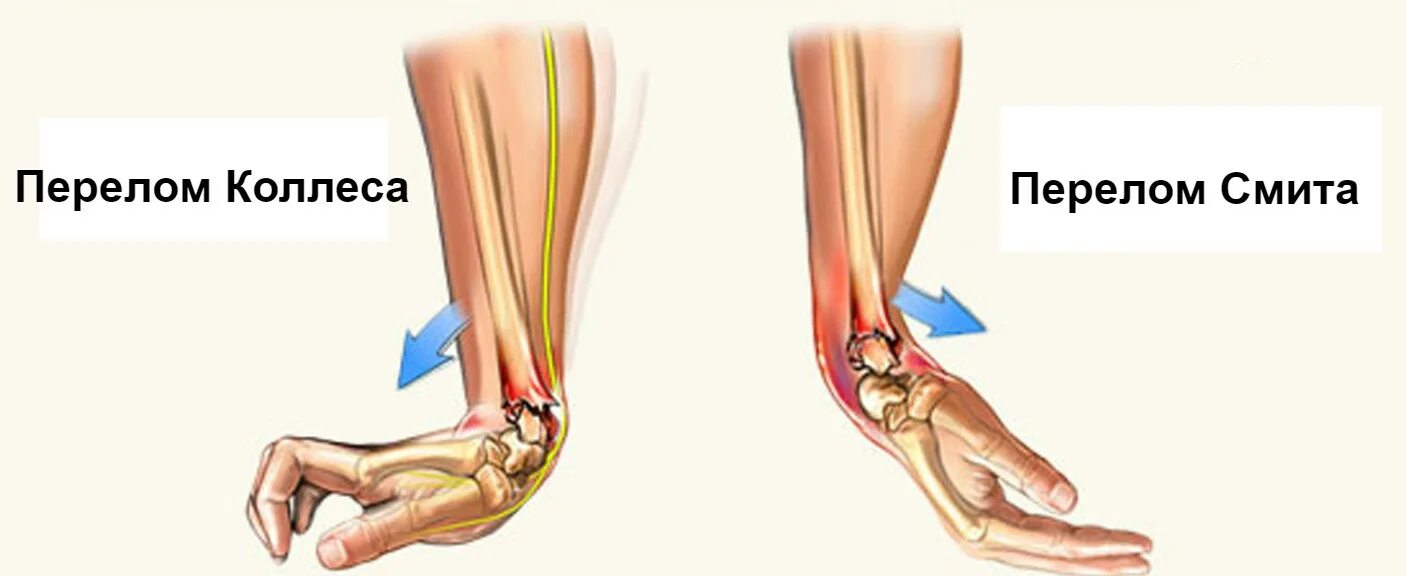

Перелом смита